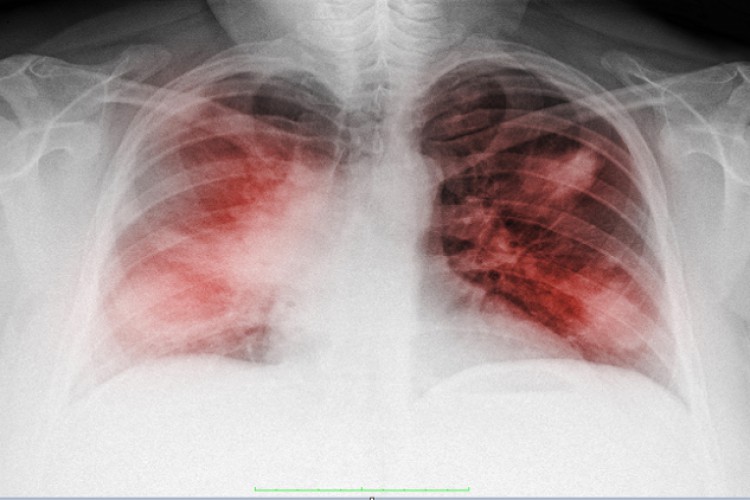

يُعرف نقص الأكسجة الصامت بأنه حالة تثير الغموض لدى الأطباء لتركها المرضى الذين يعانون من كورونا، قادرين على التحدث مع أحبائهم، بينما ينبغي أن يعانوا من أجل استنشاق الهواء.